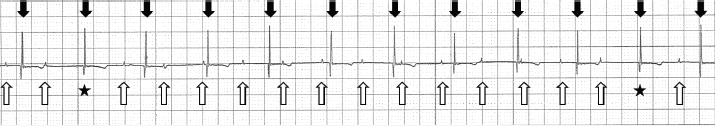

The client had not recognized seizures, collapse, or claudication. Preventive measures for fleas and ticks were regularly performed. Physical examination revealed bradycardia, but no heart murmur, fever (39.1°C), and arthritis. Blood tests revealed elevated values of leukocytes (250.5 × 102/μl) and serum amyloid A (155.3 μg/ml). Blood tests were negative for the feline immunodeficiency virus and feline leukemia virus. Since the cardiac silhouette enlargement on radiography, the cat was referred by the primary veterinarian to the department of cardiovascular medicine (Sunahara) for echocardiography. Echocardiography revealed enlargement of the left atrium [(LA)/Ao=1.6] and left ventricle (left ventricular internal diameter in diastole=1.94 cm). Other mechanical problems suggestive of myocarditis were not observed. There was no decline in local myocardial motility. Although electrocardiography (ECG) was not performed at the time of echocardiography, atrial and ventricular wall motion seemed normal. There were no findings suggestive of myocarditis at echocardiography. The cat was anesthetised to definitively determine the cause of nystagmus and torticollis. Following propofol administration for anesthesia induction and isoflurane inhalation for maintenance, the cat’s heart rate decreased to 75 beats/minute on the biomonitor. The biomonitor screen also showed that the rate of P waves was 115 beats/minute, and the rate of R waves was 75 beats/minute (Fig. 1). P waves were not associated with QRS complexes. Hence, the cat was diagnosed with third-degree AVB, and isoproterenol was administered by continuous infusion to increase its heart rate.

Fig. 1. Lead II trace on the biomonitor during anesthesia. The cat’s P waves are marked by upward arrows. The P-P intervals were consistent (0.52 seconds). The P waves that were followed by QRS complexes are indicated by asterisks. The rate of QRS complexes was 75 beats/minute (downward arrows) and their R-R intervals were consistent (0.8 seconds). QRS morphology was normal (duration, 0.04 seconds). Paper speed=25 mm/second; 1 cm=1 mV.